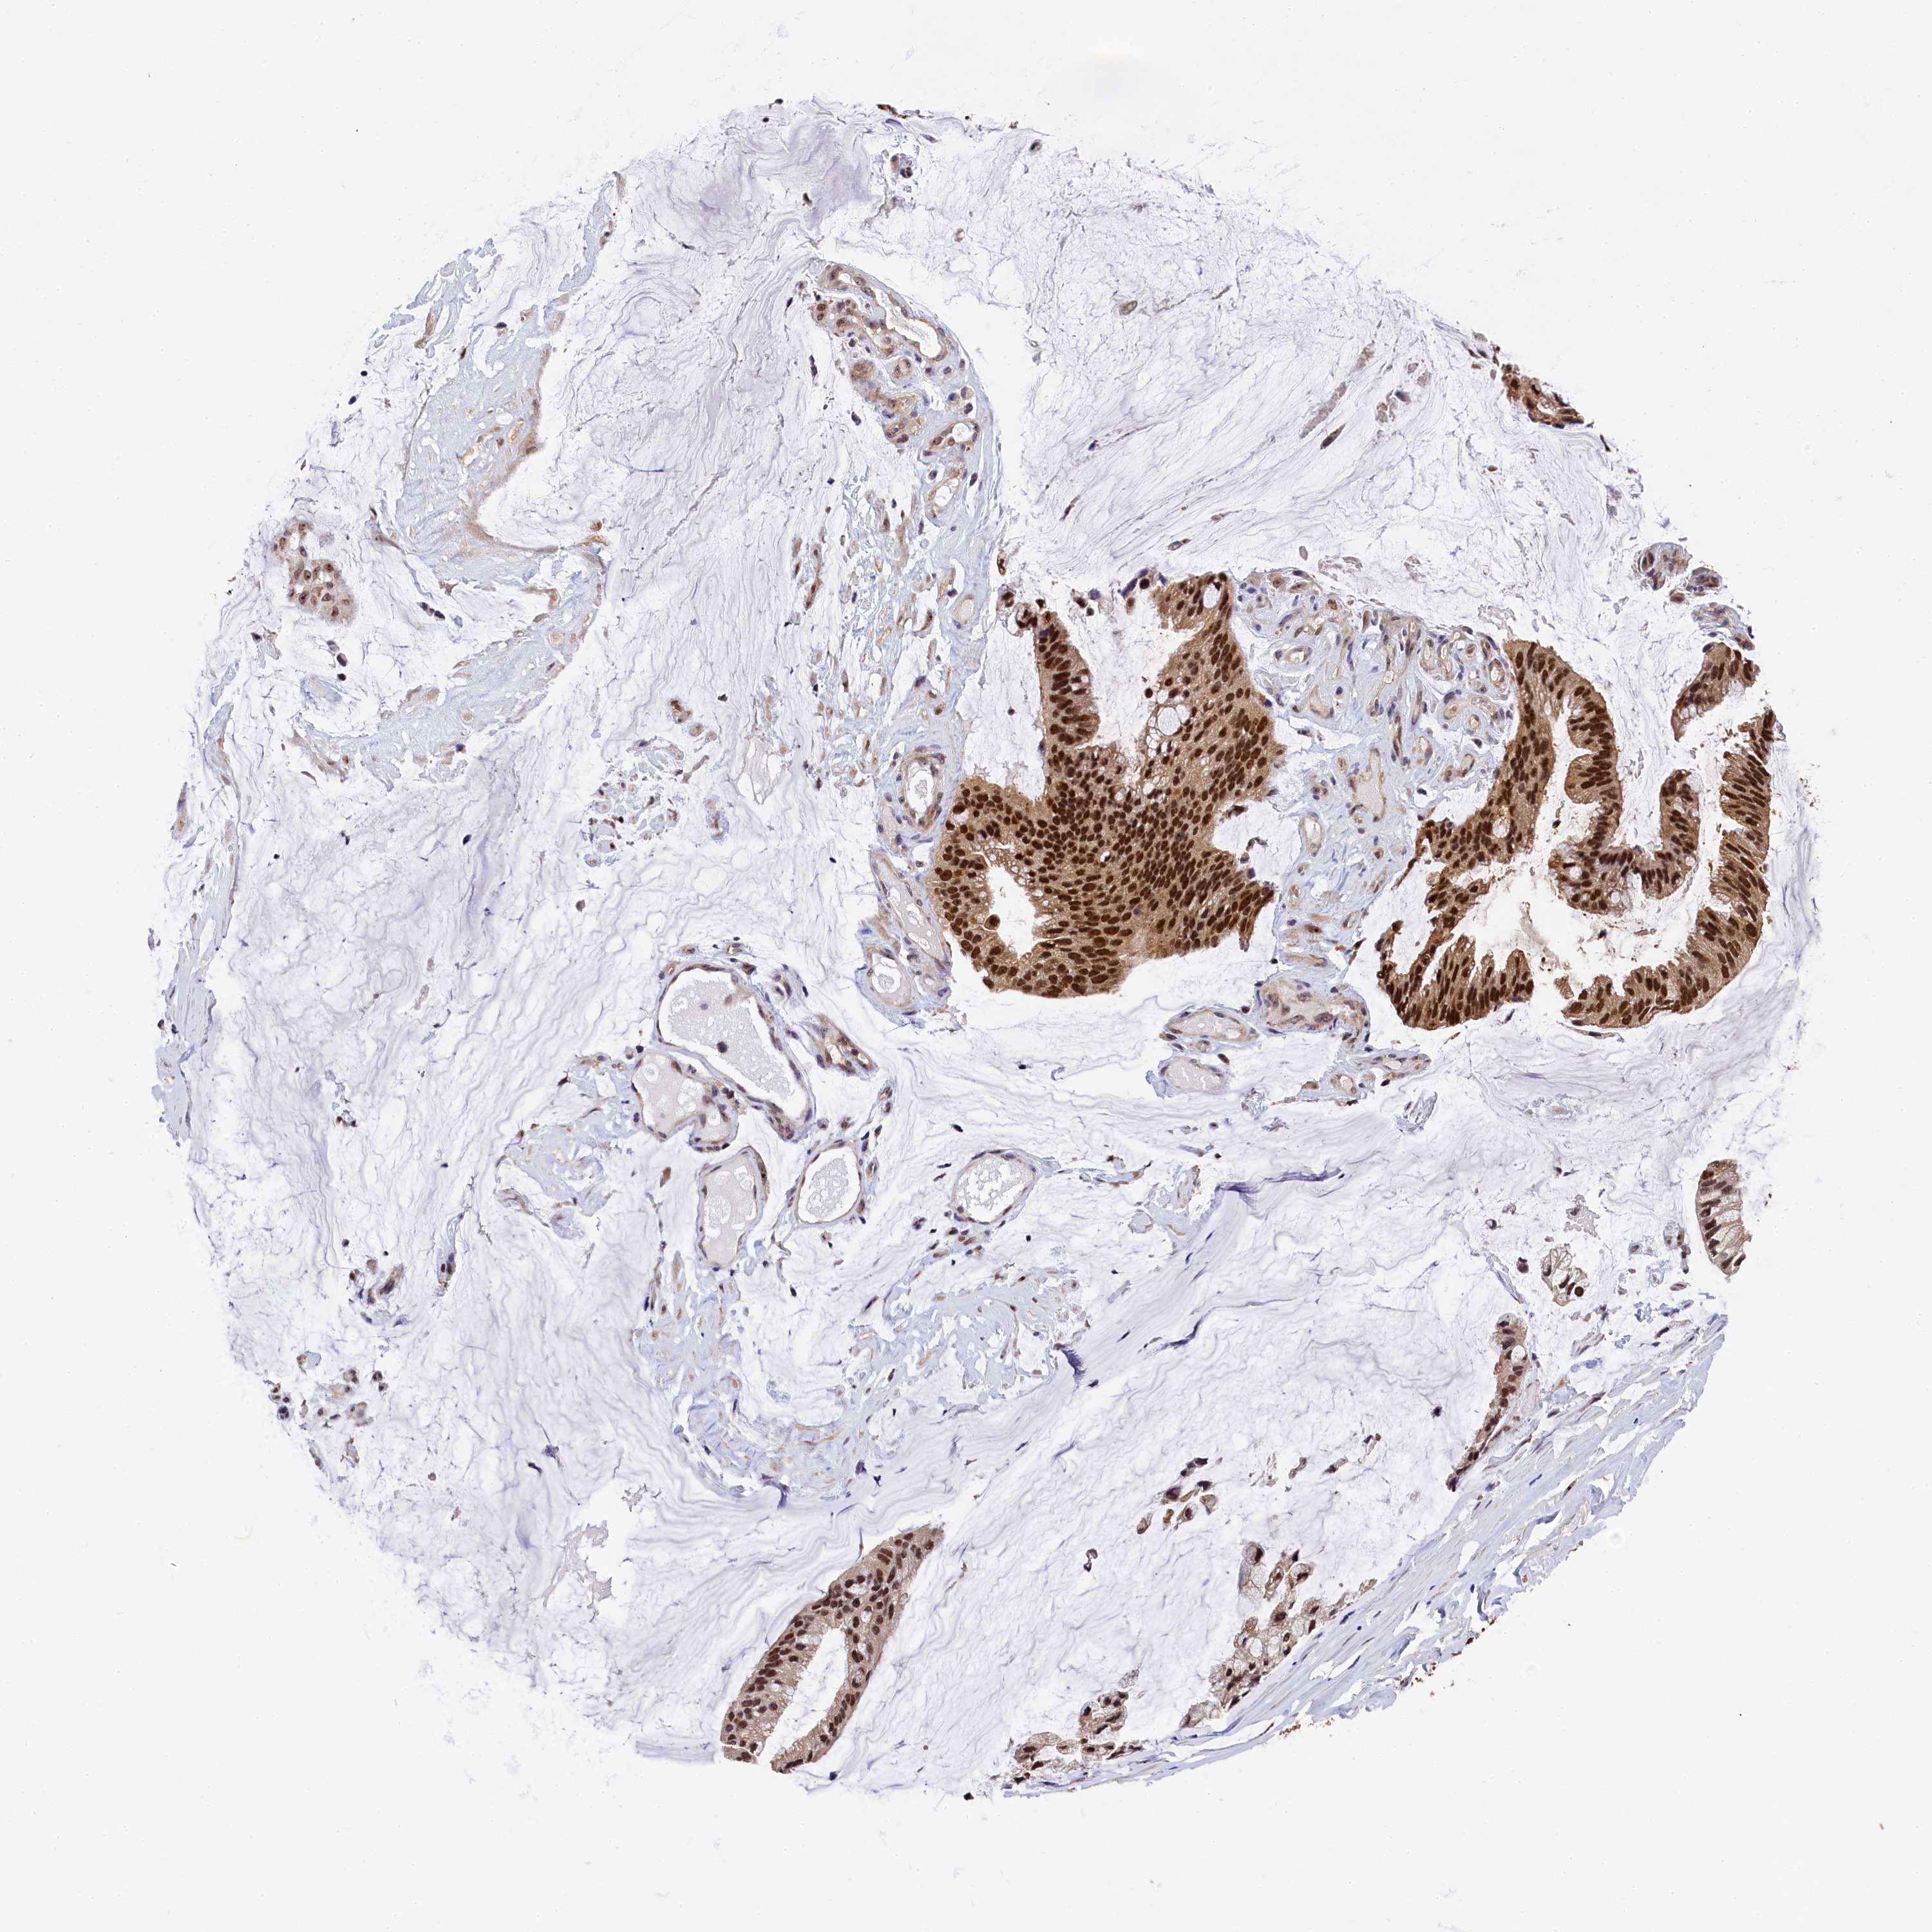

OVARIAN CANCER - Protein expressioni

A mouse-over function shows sample information and annotation data. Click on an image to view it in a full screen mode. Samples can be filtered based on level of antibody staining by selecting one or several of the following categories: high, medium, low and not detected. The assay and annotation is described here.

Note that samples used for immunohistochemistry by the Human Protein Atlas do not correspond to samples in the TCGA dataset.

Antibody stainingi

Antibody staining in the annotated cell types in the current human tissue is reported as not detected, low, medium, or high, based on conventional immunohistochemistry profiling in selected tissues. This score is based on the combination of the staining intensity and fraction of stained cells.

Each image is clickable and will lead to virtual microscopy that enables deeper exploration of all samples and also displays staining intensity scores, fraction scores and subcellular localization as well as patient and tissue information for each sample.

Antibody HPA040873

Staining

High

Medium

Low

Not detected

Intensity

Strong

Moderate

Weak

Negative

Quantity

>75%

75%-25%

<25%

None

Location

Nuclear

Cytoplasmic/membranous

Cytoplasmic/membranous,nuclear

Cystadenocarcinoma, serous, NOS

Carcinoma, endometroid

Cystadenocarcinoma, mucinous, NOS

Carcinoma, NOS